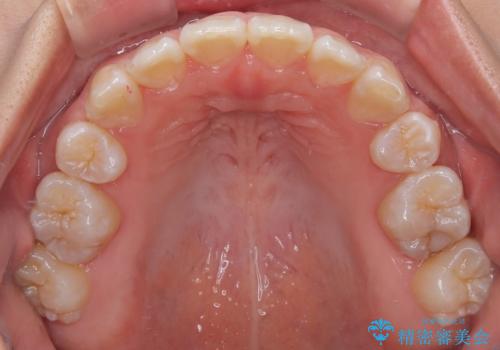

舌のトレーニングは継続して行ってもらっているため、開咬や抜歯したスペースの後戻りはなく、経過は良好です。

下顎のデコボコの解消と、真ん中の位置を改善するために左下の小臼歯を抜歯することとしました。

舌を突出する癖があり、それにより開咬が悪化したり、後戻りの原因になるため、舌のトレーニング(MFT)も行いました。